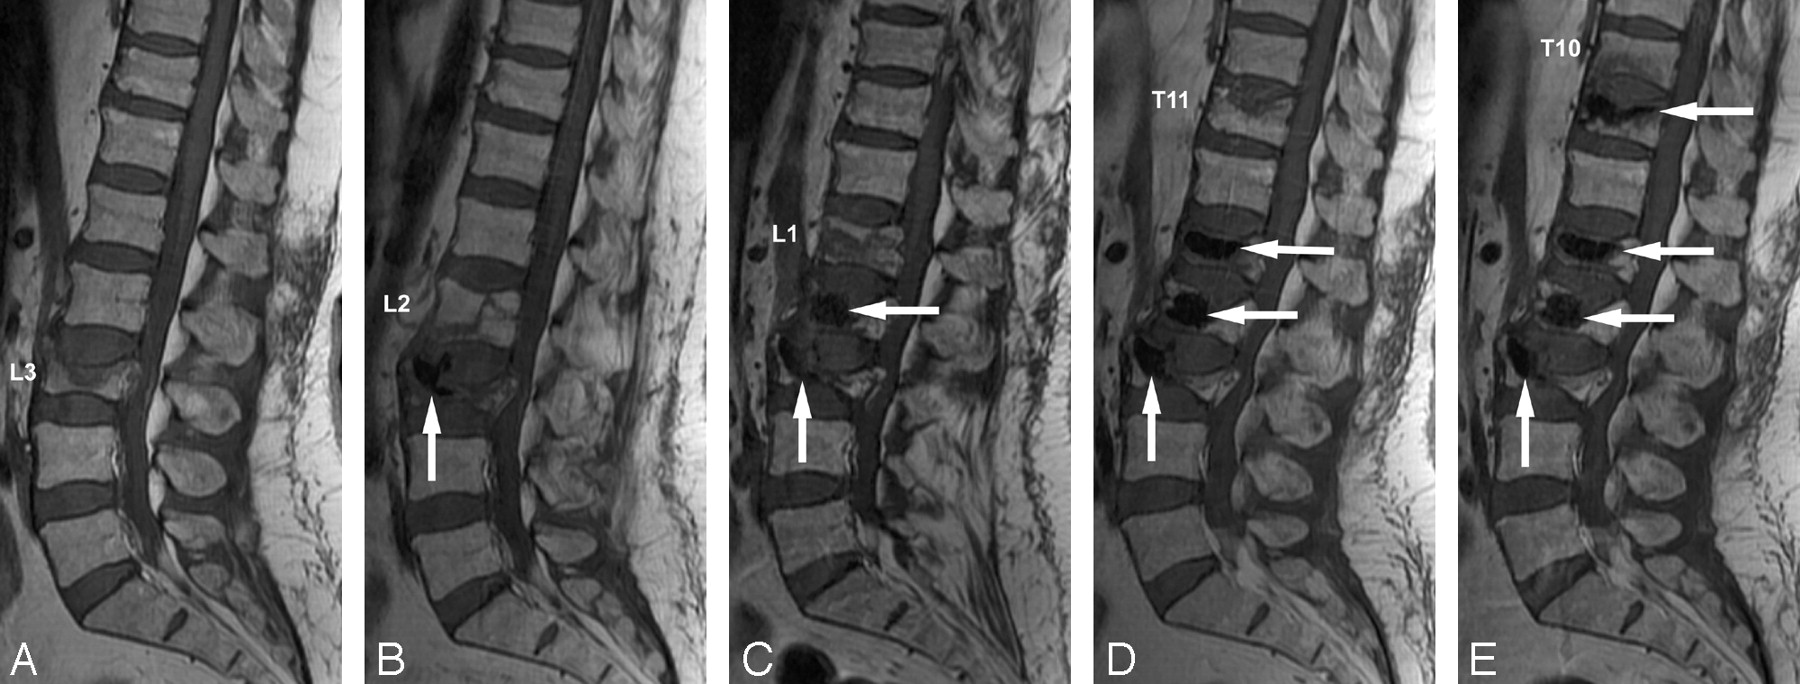

MR images of vertebrae in a 58-year-old woman with a history of long-term steroid use for treatment of a brain tumor. The patient was treated with multiple sessions of vertebroplasty.

A, Initial sagittal T1-weighted image 16 days before treatment shows an acute compression fracture of the L3 vertebral body.

B, Sagittal T1-weighted image 7 days after the initial treatment shows a new compression fracture of the L2 vertebral body. Bone cement is noted in the L3 vertebral body (arrow).

C, Sagittal T1-weighted image 22 days after the second treatment shows a new compression fracture of the L1 vertebral body. Bone cement is noted in the L3 and L2 vertebral bodies (arrows).

D, Sagittal T1-weighted image 27 days after the third treatment shows a new compression fracture of the T11 vertebral body. Bone cement is noted in the L3, L2, and L1 vertebral bodies (arrows).

E, Sagittal T1-weighted image 11 days after the fourth treatment shows a new compression fracture of the T10 vertebral body. Bone cement is noted in the L3, L2, L1, and T11 vertebral bodies (arrows).